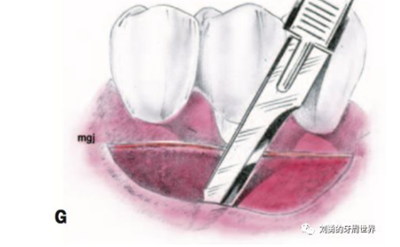

3、用15號(hào)刀片,在受區(qū)膜齦聯(lián)合的位置從遠(yuǎn)中向近中做半厚切口,刀片平行于骨面(E和F)

4、刀片按照受區(qū)的近遠(yuǎn)中長(zhǎng)度完成初始的半厚瓣全長(zhǎng)切口

5、刀片向根向繼續(xù)分離半厚瓣,冠根向延伸6-8mm,注意避讓頦神經(jīng),翻開半厚瓣如下圖: